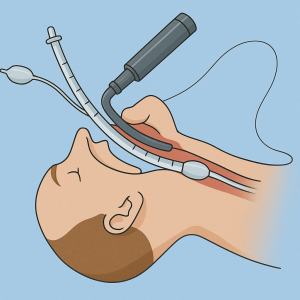

Ablauf einer endotrachealen Intubation

Ablauf einer endotrachealen Intubation

- Überprüfung von

- (Video) Larnygoskop,

- Lagerung des Patientenkopfes

- Verbesserte Jackson-Position

- ggf. Intubationskissen

- öffnen des Mundes

- ggf. Entfernen von Fremdkörpern im Mund/ Rachenraum

- Laryngoskopeinführung in den rechten Mundwinkel

- Zunge aufladen

- Laryngoskop vorschieben

- Anheben des Zungengrundes

- aufrichten der Epiglottis

- ggf. BURP Manöver

- Endotracheltubus zwischen die Simmbänder Einführen

- Tubus mit Gleitmittel versehen

- Führrungsstab mit Gleitmittel versehen

- Laryngoskop entfernen

- Führungsstab entfernen

- Visuelle Kontrolle der Tubustiefe mittels der aufgedruckten Zentimeter-Skala

- Frauen meist 20-21 cm

- Männer meist 22-23 cm

- Endotrachealtubus Blocken

- 10ml Luft

- Konnektion von Beatmungsbeutel und Endotrachealtubus

- ggf. mit Zwischenstück ( Gänsegurgel)

- Auskultation zur Kontrolle der richtigen Lage des Endotracheltubus

- ggf. Nachblocken des Cuffs

- Kapnometrie anschließen

- ist auch eine weitere Lagekontrolle

- Fiefierung des Endotracheltubus

- Beißschutz einlegen

- erneute Lagekontrolle